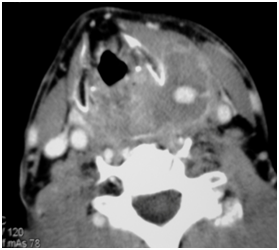

A 62-year-old man was admitted in our Otolaryngology Department of presenting sore throat, disphagia and mild dyspnea after a transesophageal ecocardiography guided cardioversion performed 3 days before. The endoscopic examination of upper aereodigestive tract showed a diffuse soft edema of arytenoids and pharyngolaryngeal tract without airway obstruction. A corticosteroid therapy was started and the symptoms quickly improved but two days later the patient presented suddenly a hemorrhage from the superior aereodigestive tract. The endoscopic examination revealed a swelling of the left lateral wall of the hypopharynx and a hemorrhage from the apex of the swelling witch stopped spontaneous after few minutes. A CT scan of neck revealed an active arterial bleeding with pseudoaneurysmal dilatation of 1,2cm of diameter arising from a fine branch of external carotid artery and a well defined homogeneously enhancing mass, 9.5 x 3.2cm diameter in left neck spaces extending superiorly to parapharyngeal spaces, inferiorly to hypopharynx displacing hyoid bone, thyroid cartilage, posterior to crycoid cartilage displacing cervical esophagus and laterally to subcutaneous tissue displacing sternocleidomastoid muscle (Figure 1). The mass was suggestive for hematoma. The angiography revealed a pseudoaneurysm with active bleeding of the terminal tract of superior thyroid artery (STA) (Figure 2). An endovascular procedure was performed with a superselctive microcateter and a endovascular occlusion by coil embolizzation of STA with exclusion of the pseudoaneurysm demonstrated at the end of the procedure (Figure 3). The symptoms resolved after one day from the endovascular procedure. The patient was discharged after two days without evidence of bleeding and an endoscopic control after 4 weeks revealed a disappearance of swelling.

Figure 1 Axial CT scan illustrating pseudoaneurysmal dilatation arising from a fine branch of external carotid artery.